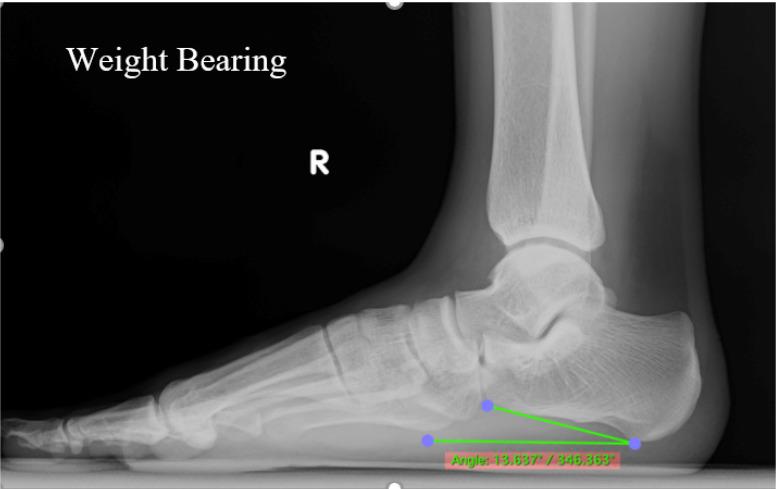

Adult-acquired flatfoot deformity (AAFD) is characterized by partial or complete flattening of the longitudinal medial arch, which develops after maturity. AAFD secondary to posterior tibialis tendon dysfunction (PTTD) is one of professional athletes' most common foot and ankle pathologies. Different modalities and procedures can be used to establish the diagnosis of AAFD and PTTD. However, imaging measurements such as the calcaneal inclination index and ultrasonography (US) of the posterior tibialis tendon (PTT) in professional athletes with medial ankle and focal pain along the PTT have yet to be widely studied. This study investigates the correlation of PTT ultrasound for evaluating PTTD with calcaneal inclination angle (CIA) for evaluating AAFD in professional athletes with medial ankle and focal pain along the PTT. Through this study, clinicians and radiologists may benefit from considering AAFD in athletes with PTTD. 112 Indonesian professional athletes with medial ankle or foot pain and focal pain along the direction of the PTT underwent foot radiography using the CIA and ankle ultrasound to observe PTT abnormalities. A negative correlation between fluid thickness surrounding the PTT and the CIA (p<0.001; 95% CI - 0.945, - 0.885), as well as a negative correlation between PTT thickness and CIA (p<0.001, 95% CI - 0.926, - 0.845), with a correlation coefficient (r) of - 0.921 and - 0.892, respectively. No significant correlation was found between PTT tear and CIA (p = 0.728; 95% CI -0.223, - 0.159; r - 0.033). This study showed a negative correlation between PTTD and AAFD via ultrasound and CIA in professional athletes with medial ankle and focal pain along the PTT. A better understanding of PTTD and AAFD imaging will lead to more effective management and prompt treatment.

成人获得性平足畸形(AAFD)的特征是内侧纵弓部分或完全扁平,这种情况在成年后出现。继发于胫后肌腱功能障碍(PTTD)的AAFD是职业运动员最常见的足踝部病变之一。可以采用不同的方式和程序来诊断AAFD和PTTD。然而,对于有内踝及沿胫后肌腱局部疼痛的职业运动员,诸如跟骨倾斜指数及胫后肌腱超声检查(US)等影像学测量方法尚未得到广泛研究。本研究调查在有内踝及沿胫后肌腱局部疼痛的职业运动员中,用于评估PTTD的胫后肌腱超声检查结果与用于评估AAFD的跟骨倾斜角(CIA)之间的相关性。通过本研究,临床医生和放射科医生在考虑患有PTTD的运动员是否存在AAFD时可能会从中受益。112名有内踝或足部疼痛且沿胫后肌腱方向有局部疼痛的印度尼西亚职业运动员接受了足部X线摄影以测量CIA,并进行了踝关节超声检查以观察胫后肌腱异常情况。胫后肌腱周围液体厚度与CIA呈负相关(p<0.001;95%CI - 0.945,- 0.885),胫后肌腱厚度与CIA也呈负相关(p<0.001,95%CI - 0.926,- 0.845),相关系数(r)分别为 - 0.921和 - 0.892。未发现胫后肌腱撕裂与CIA之间存在显著相关性(p = 0.728;95%CI -0.223,- 0.159;r - 0.033)。本研究表明,在有内踝及沿胫后肌腱局部疼痛的职业运动员中,通过超声检查和CIA发现PTTD与AAFD之间呈负相关。更好地了解PTTD和AAFD的影像学表现将有助于实现更有效的管理和及时的治疗。